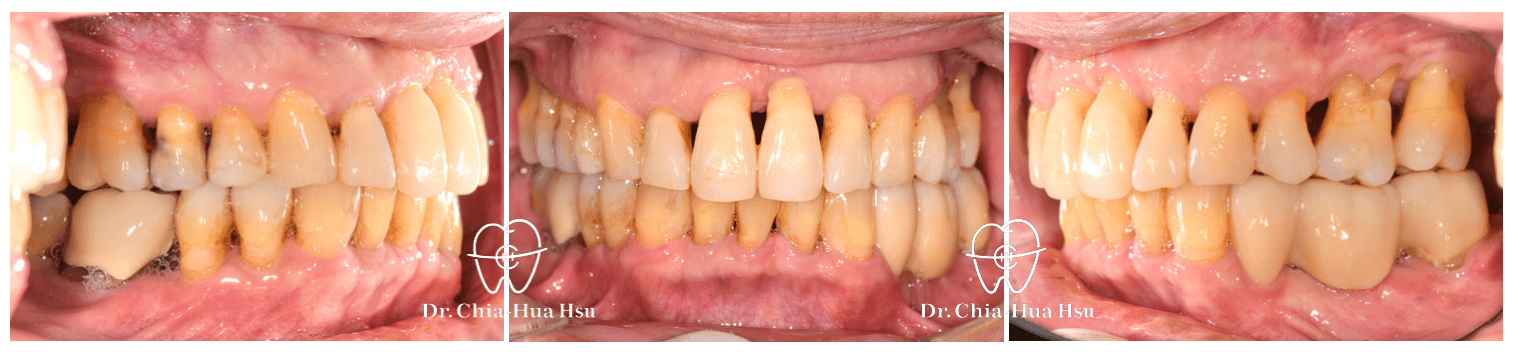

• 病患主訴:在意暴牙和牙齒不整齊。

• 問題分析:患者除了暴牙、牙齒不整齊和黑三角縫明顯,還有牙周病的問題。

• 治療方式:在病患牙周治療結束後,與患者討論治療方案,最後使用對牙周健康友善的隱適美治療,並搭配上顎骨釘的使用,來改善患者的暴牙與齒列不正。後續也透過美學樹脂補牙來處理患者下顎門牙黑三角縫的問題。

• 治療結果:在與牙周病科醫師、牙體復形科醫師的協同治療下,改善患者暴牙和齒列不正,恢復患者的牙周健康與美觀。

治療前

治療後